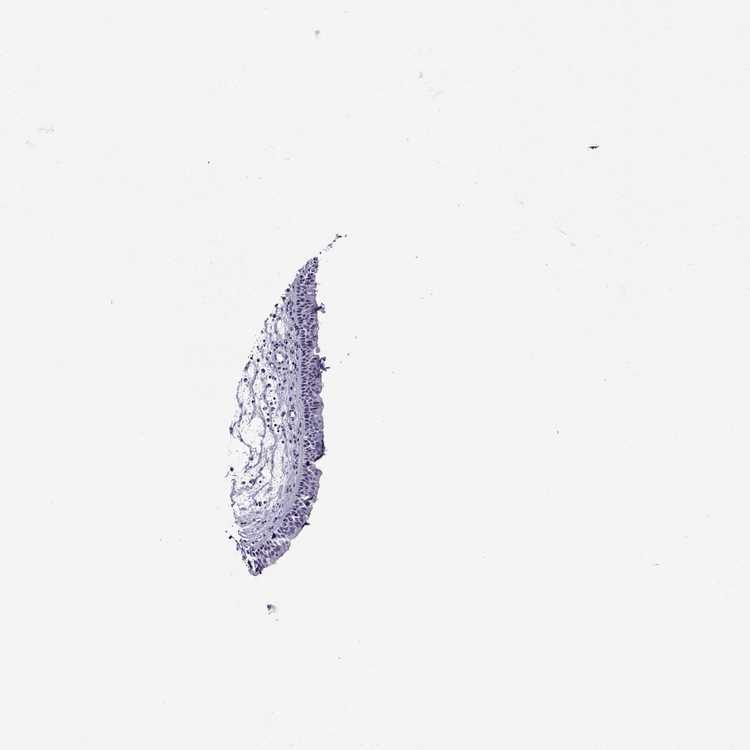

TISSUE PRIMARY DATA NASOPHARYNX Show tissue menu

NASOPHARYNX - Antibody stainingi

Antibody staining in the annotated cell types in the current human tissue is reported as not detected, low, medium, or high, based on conventional immunohistochemistry profiling in selected tissues. This score is based on the combination of the staining intensity and fraction of stained cells.

Each image is clickable and will lead to virtual microscopy that enables deeper exploration of all samples and also displays staining intensity scores, fraction scores and subcellular localization as well as patient and tissue information for each sample.

Antibody HPA003448Antibody CAB010058

Respiratory epithelial cells Not detectedNot detected